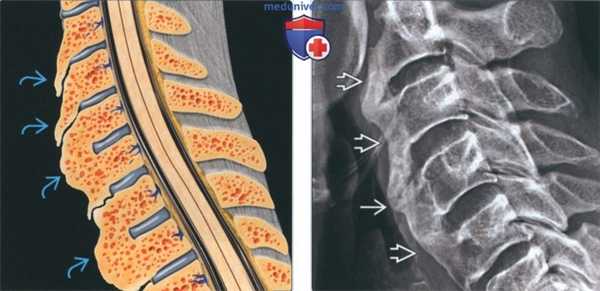

(Слева) Рисунок, сагиттальная проекция: признаки диффузного идиопатического скелетного гиперостоза (ДИСГ) в шейном отделе позвоночника. К основным параметрам, свидетельствующим в пользу патологических изменений, относятся: наплывающая передняя оссификация, которая часто связывает тела позвонков по ходу неповрежденных дисков и нормальных дугоотростчатых суставов.

(Справа) Рентгенография в боковой проекции: наплывающая оссификация в грудном отделе позвоночника. Несмотря на то, что большинство позвонков характеризуются оссификацией, выраженной спереди на всем протяжении тела, как минимум в структуре одного из них визуализируется углубление с зоной просветления. (Слева) КТ, сагиттальная проекция: типичная для ДИСГ наплывающая передняя оссификация. Этот пациент 81 года упал с кровати. Сочетание сращения позвонков по ходу позвоночного столба с остеопорозом поспособствовало перелому. У 40% таких пациентов при переломе будет отмечаться неврологический дефицит, а уровень смертности в течение трех месяцев составляет 20%.